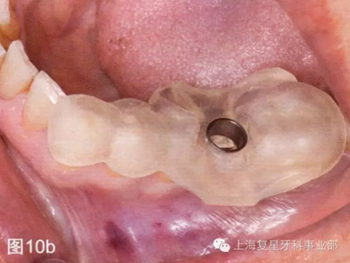

引導(dǎo)板一制作完成,就在模型上進行試戴,檢查其有無不密合的地方以及在對引導(dǎo)板和BioHorizons引導(dǎo)手術(shù)工具包消毒之前有無手術(shù)進入困難(圖10a)。

圖10a:術(shù)前在模型上進行外科引導(dǎo)檢查

第二天患者就診進行手術(shù)。用0.12%葡萄糖酸氯已定漱口水(Oralgene,Laboratorios Maver)含漱2分鐘后,進行消毒和術(shù)區(qū)的準(zhǔn)備,在缺牙區(qū)(36#牙區(qū)域)的頰舌側(cè)和頂部進行局部麻醉(2%鹽酸利多卡因和1:100000腎上腺素)。幾分鐘后,置入外科導(dǎo)板,在外科導(dǎo)板上的孔洞中置入中空的圓柱形金屬引導(dǎo)管,然后引導(dǎo)軟組織打孔器進入,其轉(zhuǎn)速為1200rpm。然后去除引導(dǎo)板,用剝離子去除截面的軟組織,并浸泡在鹽溶液中(圖10b-d)。

圖10b:將外科導(dǎo)板放在手術(shù)部位